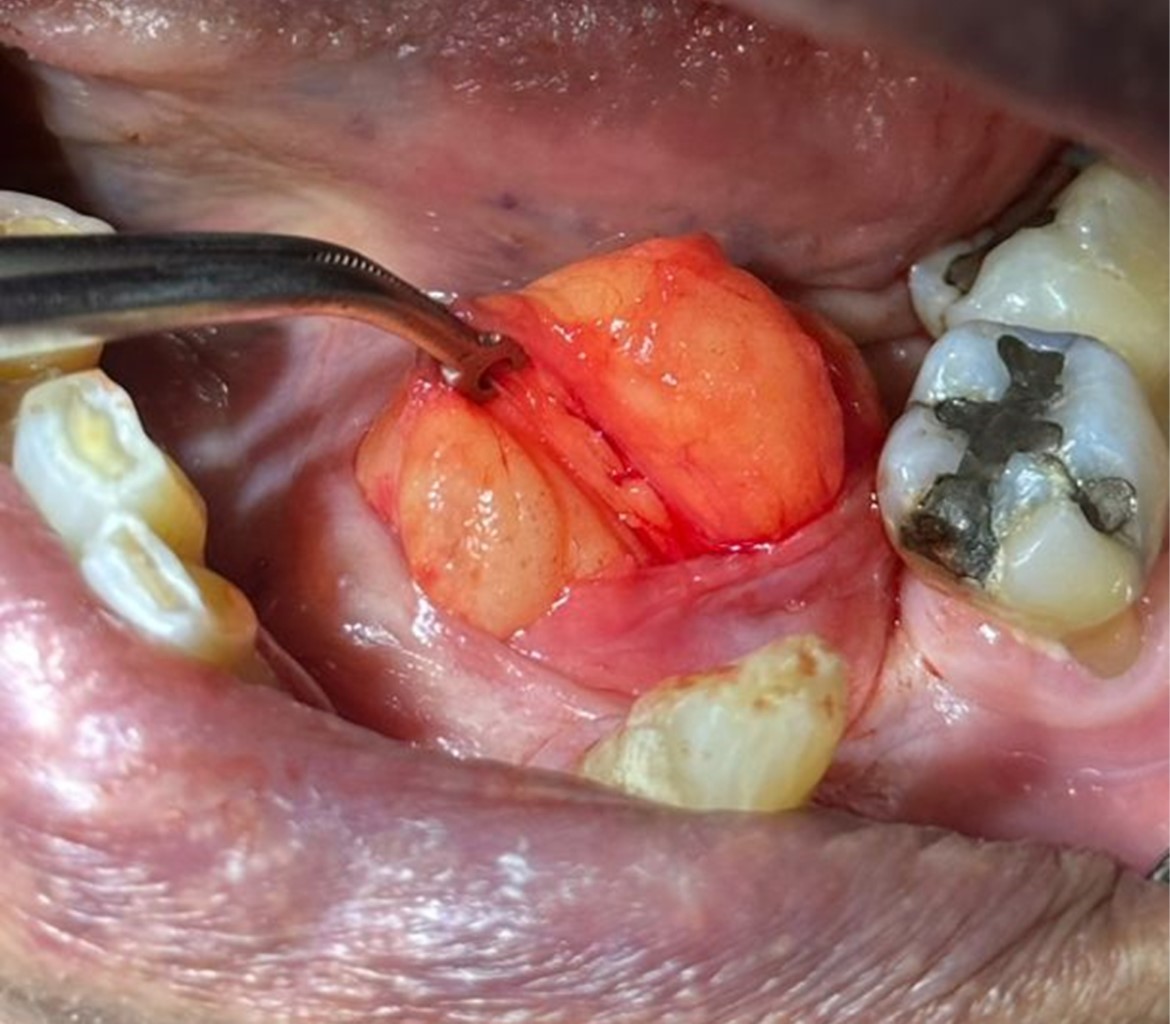

En el examen clínico extraoral no se evidenciaron aumentos de volumen ni asimetrías faciales. Durante examen clínico intraoral se evidenció aumento de volumen de color amarillento en piso de boca, con predominio del lado izquierdo, circunscrito, depresible a la palpación, con un tamaño aproximado de 3 × 2 cm de diámetro (Figura 1).

Basado en los hallazgos clínicos, un diagnóstico diferencial clínico de Lipoma fue dado, donde posteriormente se decidió la realización de toma de biopsia excisional de lesión bajo anestesia local (Figura 2).

Figura 2